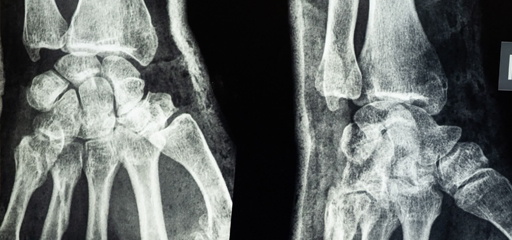

Paris'teki Georges Pompidou hastanesindeki kıdemli bir ortopedi cerrahının hastasının ön kolunda kemiğe yakın bir Kalaşnikof mermisini gösteren bir röntgenini bir NFT dijital sanat eseri olarak satışa sunduğu ortaya çıktı.

Dr. Emmanuel Masmejean, röntgenin sahibini erkek arkadaşını müzik alanında DEAŞ’ın silahlı üyelerinin saldırısına kaybeden genç bir kadın olarak nitelendirmişti.

Hürriyet'teki habere göre; İsminin açıklanmasını istemeyen kadın adına konuşan avukatı Elodie Abraham, “Bu doktor, bu hastaya karşı tıbbi sır tutma görevini çiğnemekle yetinmeyip, bu genç kadının özel hayatını tanımlamanın iyi bir fikir olacağını düşündü ve onu mükemmel bir şekilde teşhis etti” dedi.

Avukatı ayrıca Masmejean'ın pazar günü müvekkilini arayıp "ona karşı en ufak bir pişmanlık veya empati ifade etmeden kendisini haklı çıkarmaya çalıştığını" söyledi.

Dr. Masmejean, hastasından izin istemeden bilgilerini paylaştığı için yasal işlem ve disiplin suçlamasıyla karşı karşıya olduğu bildirildi.

Haberi yapan Mediapart’a göre, ilan kaldırılmadan önce röntgen filmi OpenSea internet sitesinde 2 bin 776 Dolar fiyatla satışa sunulmuştu.